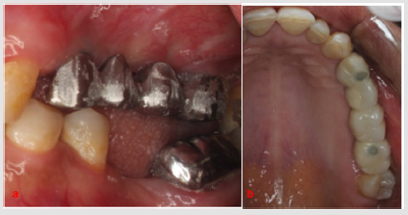

A 40-year-old female patient was referred to the Prosthodontics department in our School of Dentistry in January 2018. The patient’s informed consent was obtained to include her photographs and radiographs in our study. Intra-oral examination of the maxillary arch (Figure 1) revealed multiple carious lesions which were restored with composite resin. Remaining roots of maxillary left premolars and first molar as well as non-restorable maxillary left second molar, due to extensive subgingival caries, were extracted. Implants insertion was delayed for 6 months after extraction to allow for complete remodeling of the extraction sockets. CBCT requested two weeks prior to implants’ placement showed slightly deficient bone bucco-lingually in the maxillary left first premolar region (Figure 2A). Furthermore, diminished bone height (4.19 mm) was evident in the left second molar region (Figure 2B). Hence, densah bur was used for ridge expansion and crestal sinus lift in the left first premolar and second molar respectively.

Figure 1: Intra-oral maxillary occlusal view showing carious right and left lateral incisors as well as left canine, remaining roots of left premolars and first molar and nonrestorable left second molar.

Peri-apical x-rays were taken prior to implant surgery for comparative purposes (Figure 2C). In the first premolar region, drilling using Densah burs (VS8) proceeded under counterclockwise pumping motion (Figure 3A). During insertion of the final drill (3.5×11.5 mm), fenestration of the buccal wall of the osteotomy occurred. Implant (4×11.5 mm) (Neobiotech, Korea) was inserted and the dehiscence was managed by grafting with DM Bone (Neobiotech, Korea) and T-Gen membrane (SK bioland Co., Korea) (Figure 3B). In the second molar region, pilot drill was inserted 1 mm short of the sinus membrane. Particulate DM Bone was packed into the prepared osteotomy. Sequential drilling then proceeded employing 200 rpm speed without irrigation, so that the densah bur can push the grafts coronally (Figure 4A & 4B). The compacted grafts lifted the sinus membrane gradually until reaching the desired height (8 mm), followed by implant (4×7.3 mm) insertion (Figure 4C). Implant stability quotient (ISQ) of both implants was measured on the day of surgery, 3 and 6 months postoperatively (Ostell, Sweden) (Table 1). After 6 months, the implants were restored with porcelain fused to metal screw-retained bridge using CCM UCLA abutments (Neobiotech, Korea) (Figure 5A & 5B). The patient was followed-up for a period of six months with no complications.

Figure 5: Screw-retained porcelain fused to metal bridge. a. A: Intra-oral profile view of the metal try-in, b. B: Occlusal view showing final bridge with composite sealing the access holes.